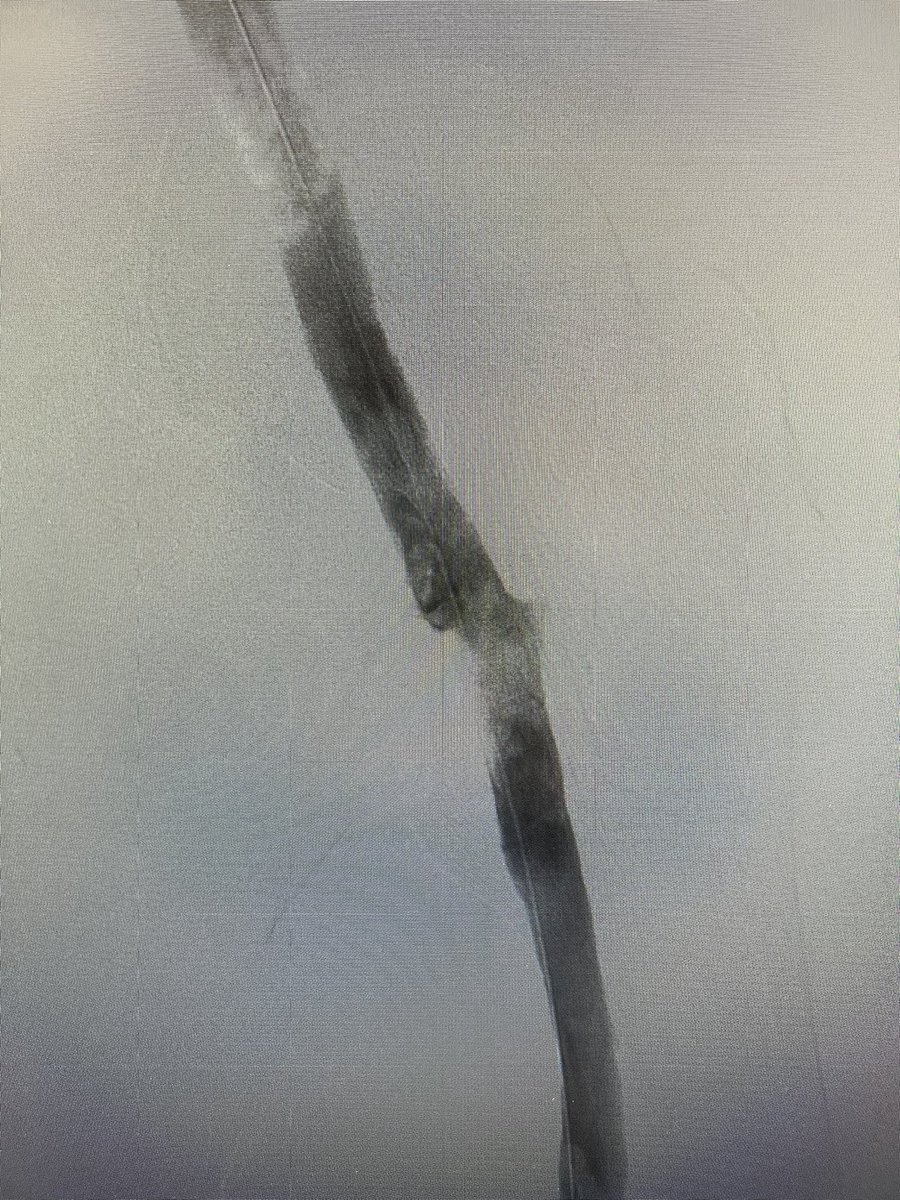

48y, ílio-popliteal dvt, symptomatic. angiographic control after ClotTriever. No thrombolytic, no cti needed. @InariMedical